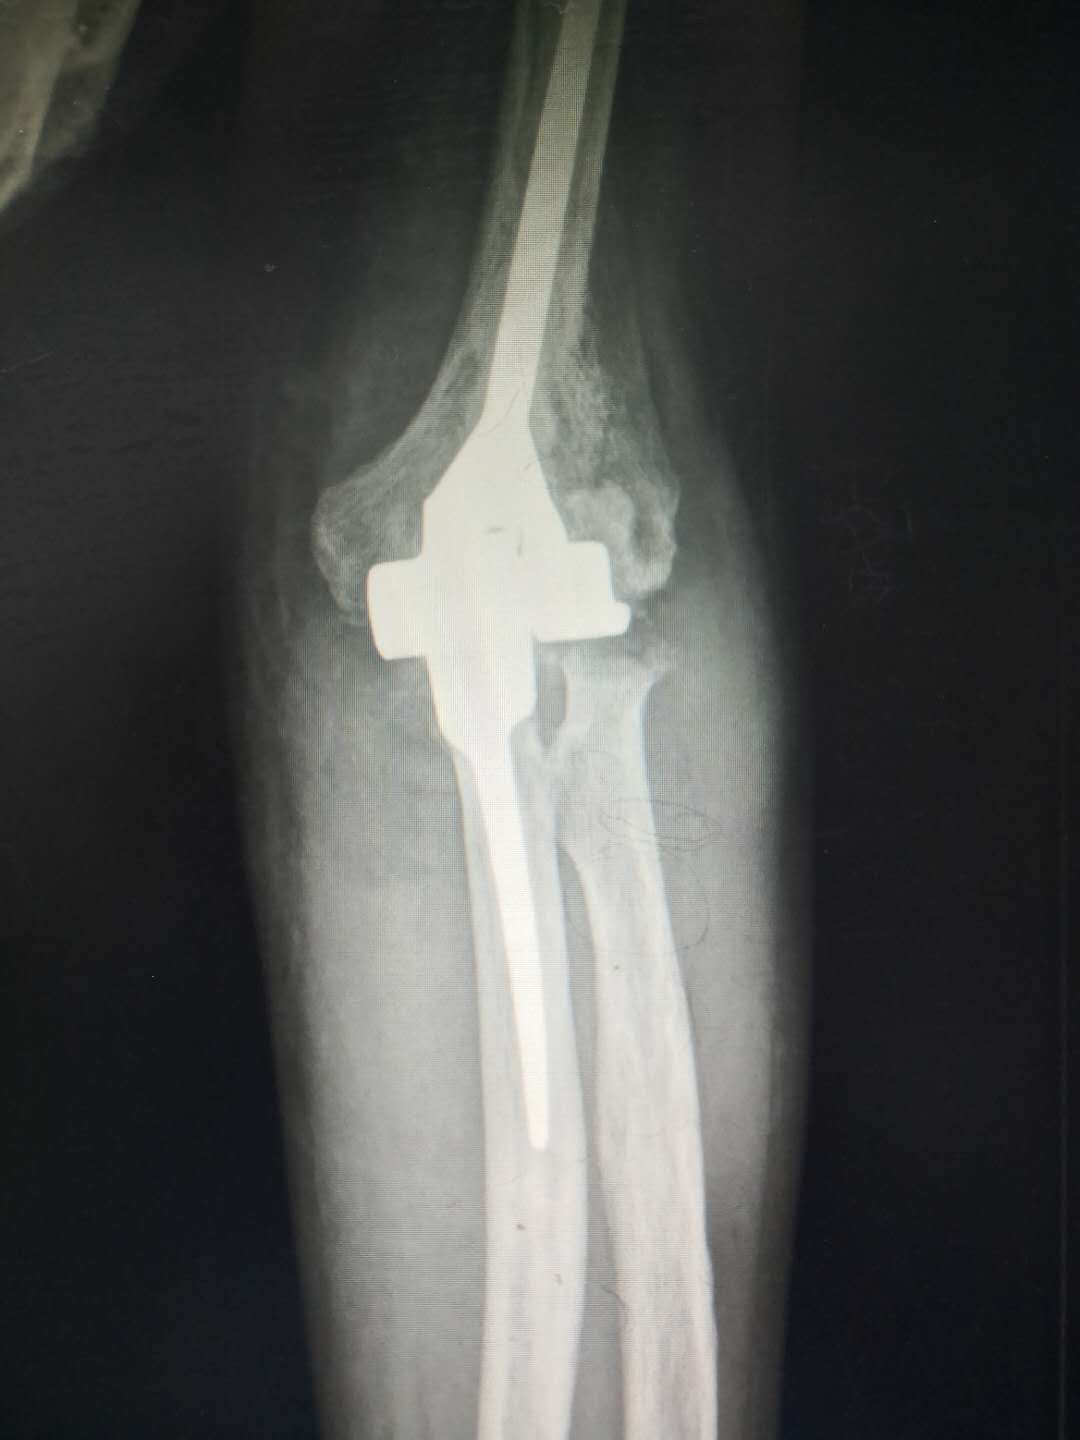

人工肘关节置换术